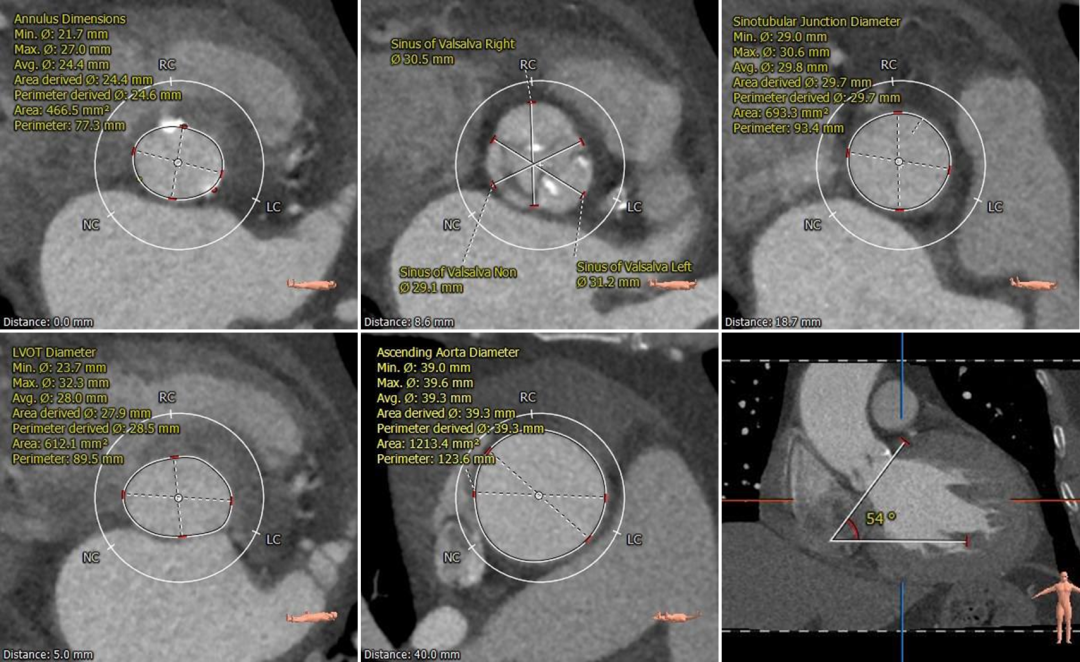

术前CT评估

三叶式主动脉瓣,中度钙化,主要分布于左右窦窦底并延伸到瓣环-流出道水平,无冠窦发育畸形,窦内空间小;

双侧冠脉开口高度可,切线角度测量,左窦瓣叶略长于左冠开口到瓣叶根部距离;

无冠窦内径略小,左右窦内径可,窦管交界、升主动脉内径可;

非横位心,主动脉弓宽度角度可;

根部测量

瓣环平均径24.6mm,STJ、升主内径可,非横位心

冠脉测量

冠脉开口高度可,切线位测量左窦瓣叶略长于左冠开口

钙化分布

中度钙化,HU 600 629mm³,HU850 182mm³

弓部及入路